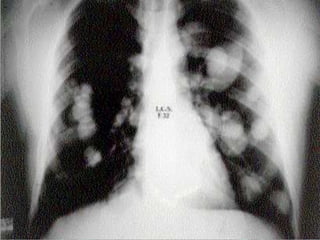

Pneumonia

• Infiltrados pulmonares;

• Opacificação

homogênea dos lobos ou

segmentos envolvidos;

• Broncograma aéreo;

• Múltiplas opacidades;

• Processo inflamatório e

infeccioso.

Pneumonia • Infiltrados pulmonares; •Opacificação homogênea dos lobos ou segmentos envolvidos; • Broncograma aéreo; • Múltiplas opacidades; • Processo inflamatório e infeccioso.